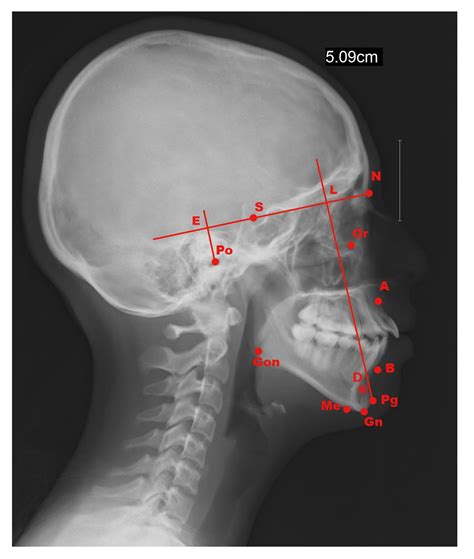

Interpreting a Cephalometric X Ray requires a thorough understanding of craniofacial anatomy and orthodontic principles. The orthodontist analyzes various landmarks and measurements to assess the patient’s dental and skeletal relationships. Some of the key landmarks and measurements include:

Key Landmarks

The following table outlines some of the key landmarks used in Cephalometric X Ray analysis:

Landmark Description

Sella (S) The center of the sella turcica, a depression in the sphenoid bone

Nasion (N) The most anterior point of the frontal bone at the nasofrontal suture

Orbitale (Or) The lowest point on the inferior margin of the orbit

Pogonion (Pog) The most anterior point on the chin

Gnathion (Gn) The most inferior point on the symphysis menti

Key Measurements

The following measurements are commonly used to assess dental and skeletal relationships:

• SNA angle: Measures the relationship between the maxilla and the cranial base

• SNB angle: Measures the relationship between the mandible and the cranial base

• ANB angle: Measures the relationship between the maxilla and the mandible

• Wits appraisal: Measures the anteroposterior relationship of the maxilla and mandible

• Gonial angle: Measures the angle of the mandible